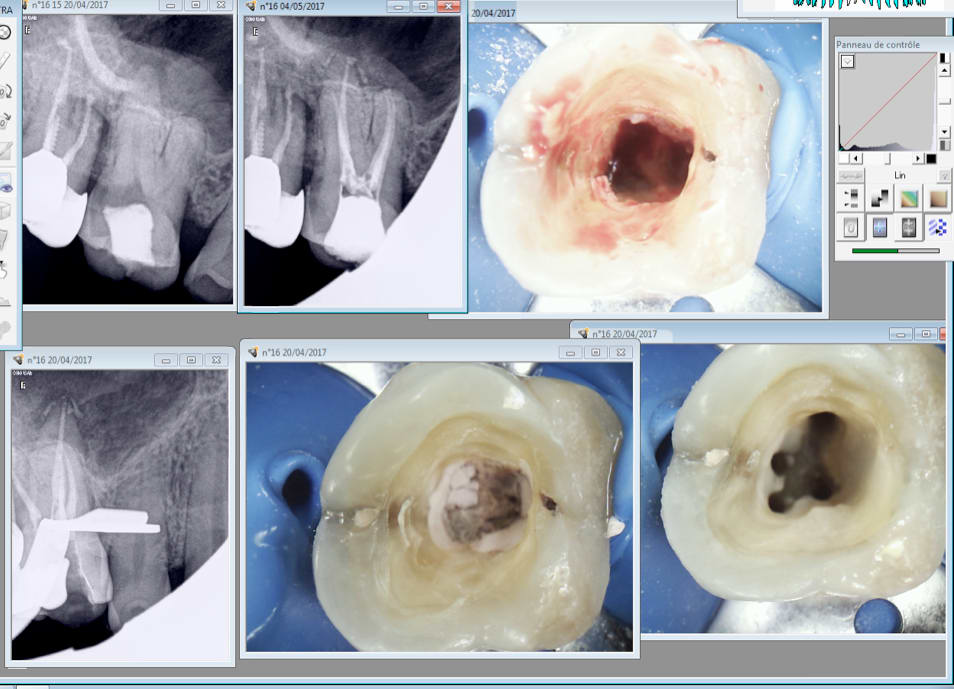

Tu tombes bien toi. Nouveau patient vu en urgence à la fac ou a été réalisée une ouverture de chambre légèrement "distalée" comme tu peux le constater. La douleur s'est amplifiée curieux non ? -)

Je fais quoi ? J'apporte ma modeste contribution à l'édifice qualité en incitant le patient à entamer une procédure contre la FAC ? -)

Ton comportement est inadmissible tu n'es pas juge et parti et ca va certainement te retomber sur la tronche un jour.

Tu me donnes combien sur 20 en endo "professeur" ? -)